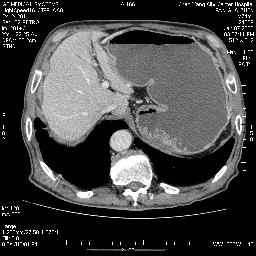

女,74岁,呕吐10余日

肝胰壶腹占位,考虑-壶腹癌!

胃体部粘膜不规则增厚,胃肠造影也显示充盈缺损-胃溃疡?胃癌?

病变主要位于钩突(癌)。如是壶腹部,肝内外胆管扩张明显。

十二指肠降段扩张,水平段狭窄成鼠尾状,肠壁明显增厚,胰腺勾突增大成不均匀强化,其内可见低密度区,胆囊增大,1十二指肠水平段腺癌侵犯胰腺勾突可能大,2胰腺癌侵犯十二指肠(只有胆囊增大没有肝内外胆管扩张不好解释)代除外.

十二指肠降段扩张,水平段狭窄成鼠尾状,肠壁明显增厚,胰腺勾突增大成不均匀强化,其内可见低密度区,胆囊增大,1十二指肠水平段腺癌侵犯胰腺勾突可能大,2胰腺癌侵犯十二指肠 。

今日手术结果:胰腺钩突癌侵犯十二直肠,腹腔淋巴结转移.